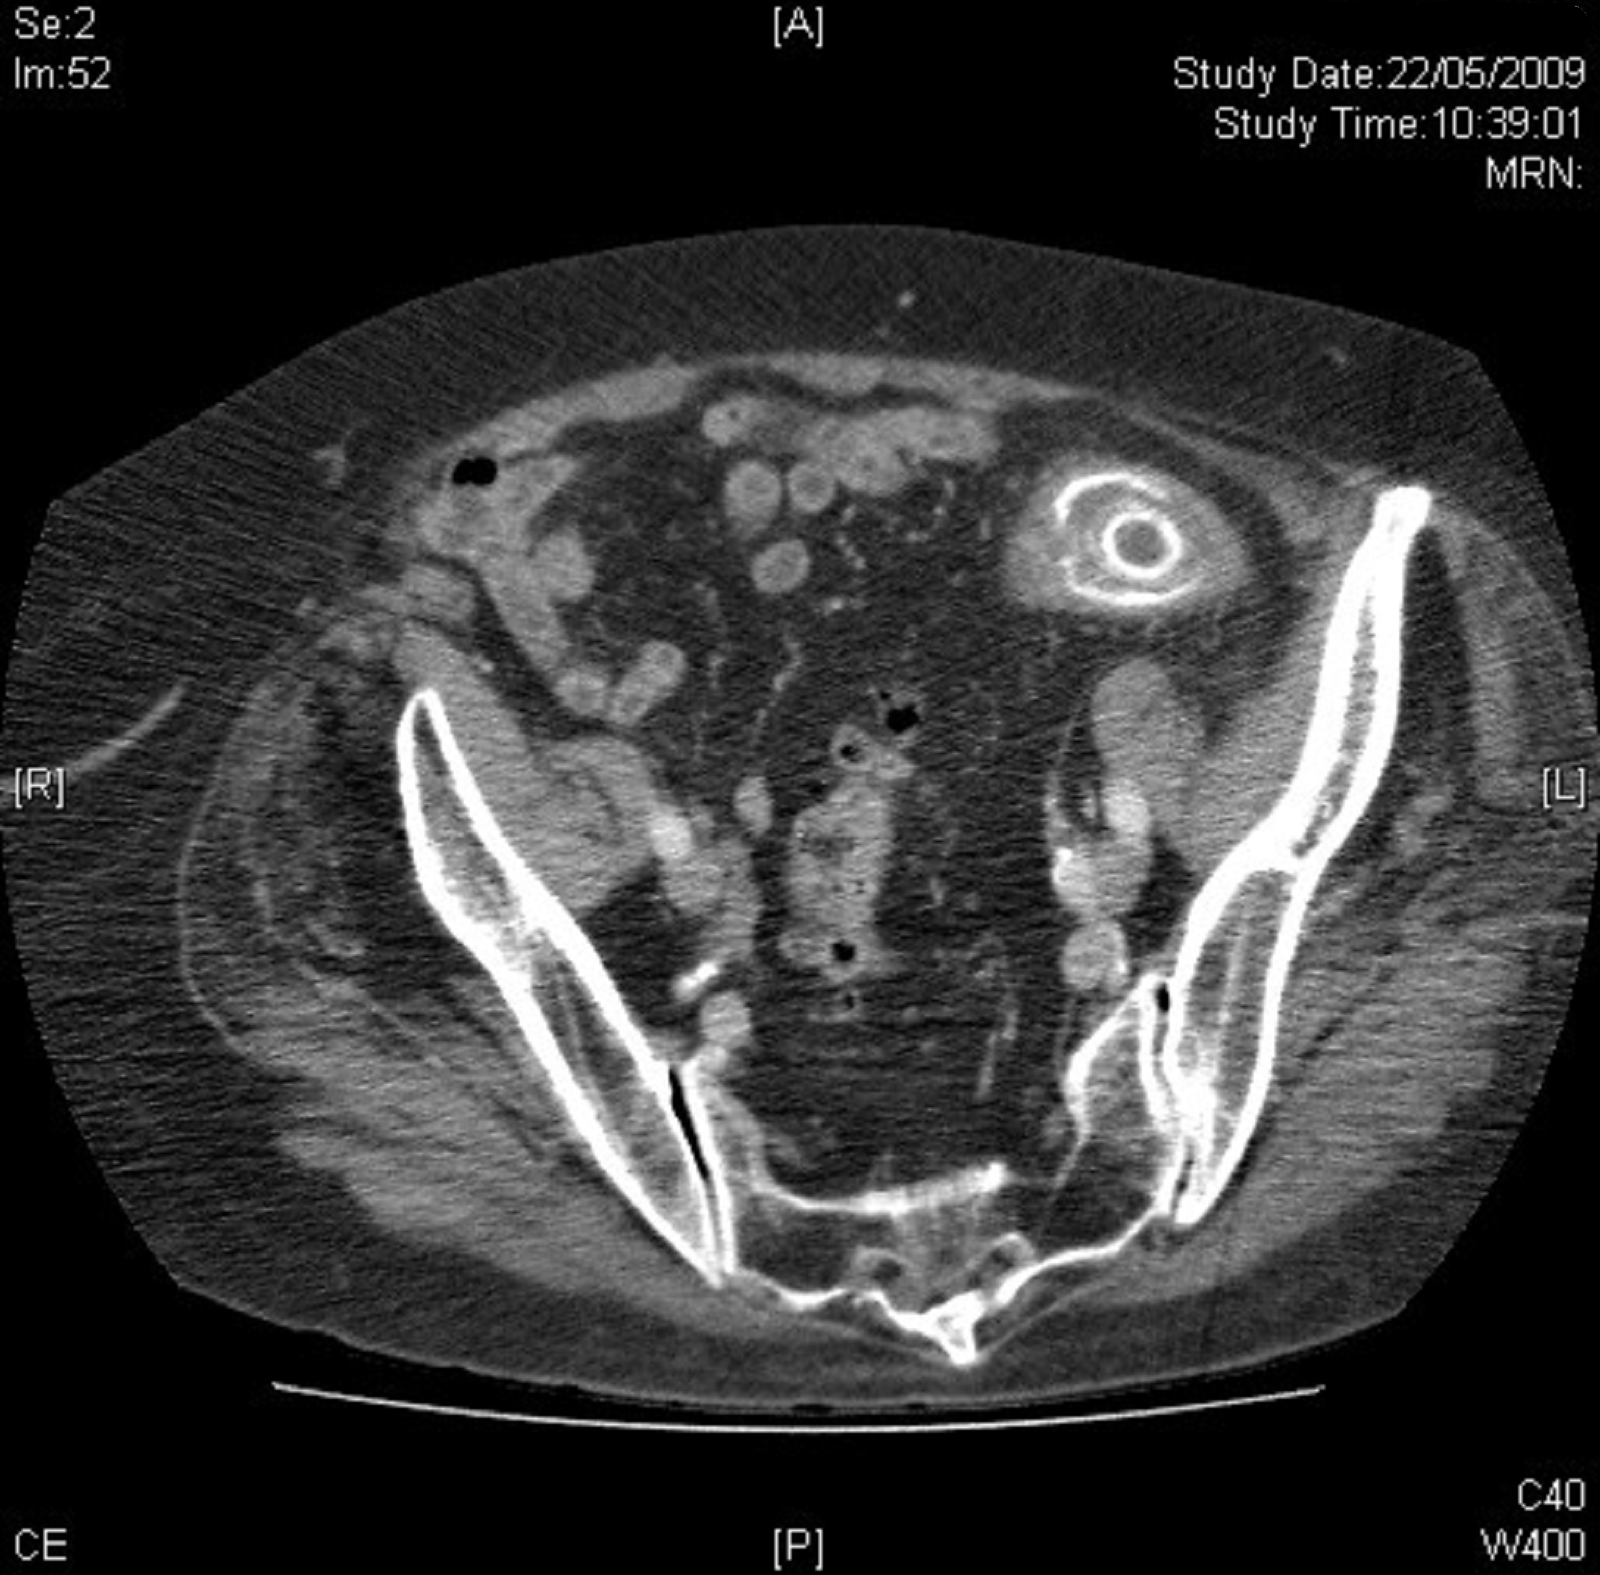

(PDF) Sigmoid laser lithotripsy for gallstone ileus Gallstone Endoscopic Laser Lithotripsy — in conclusion, this procedure shows that endoscopic laser lithotripsy and lithotomy is safe and feasible for. — the utilization of laser lithotripsy under biliary endoscopic guidance has emerged as a promising treatment for. — introduction —laser lithotripsy of bile duct stones has become a widely accepted endoscopic treatment modality for giant, impacted, or very hard. Five. Gallstone Endoscopic Laser Lithotripsy.